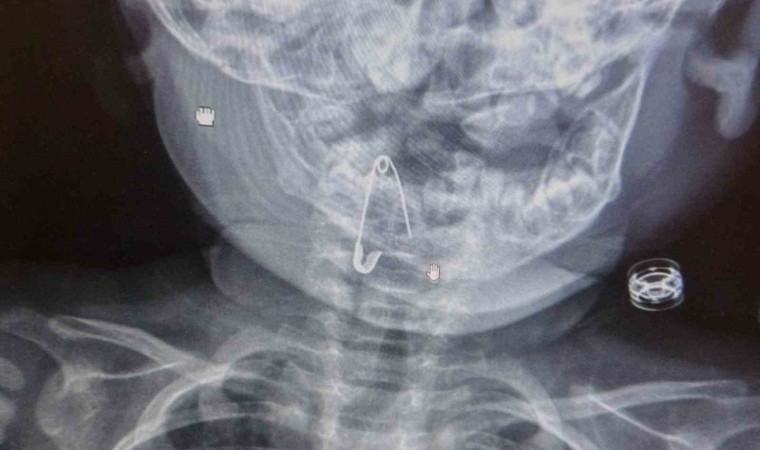

Güroymak ilçesinde 8 aylık bebek, evde bulunan çengelli iğneyle oynarken onu yuttu. Öksürmeye başlayan minik çocuğun, hastanede çekilen röntgen sonucu çengelli iğneyi yuttuğu fark edildi. Güroymak Devlet Hastanesi’nden Tatvan Devlet Hastanesi’ne ambulansla sevki gerçekleşen minik çocuk, Kulak Burun Boğaz Hastalıkları Uzmanı Operatör Dr. Hakan Tuhan tarafından yapılan başarılı operasyonla sağlığına kavuştu. Çengelli iğnenin saplı olduğu soluk borusundan çıkarılan bebek, 2 saatlik gözlemin ardından taburcu edildi.

Konuyla ilgili açıklamada bulunan Kulak Burun Boğaz Hastalıkları Uzmanı Operatör Dr. Hakan Tuhan, “8 aylık bir bebek, Bitlis’in Güroymak ilçesinden tarafımıza danışıldı. Güroymak ilçesinde çekilen röntgen sonucunda çengelli iğnenin soluk borusunun girişinde olduğunu teyit ettik. Yapılan müdahaleler sonucunda çengelli iğneyi çıkardık. Çıkardıktan sonra iki saat kadar gözlem altında tuttuk hastamızı. Daha sonrasında herhangi bir komplikasyonla karşılaşmadık ve sorunsuz bir şekilde taburcu ettik” dedi.